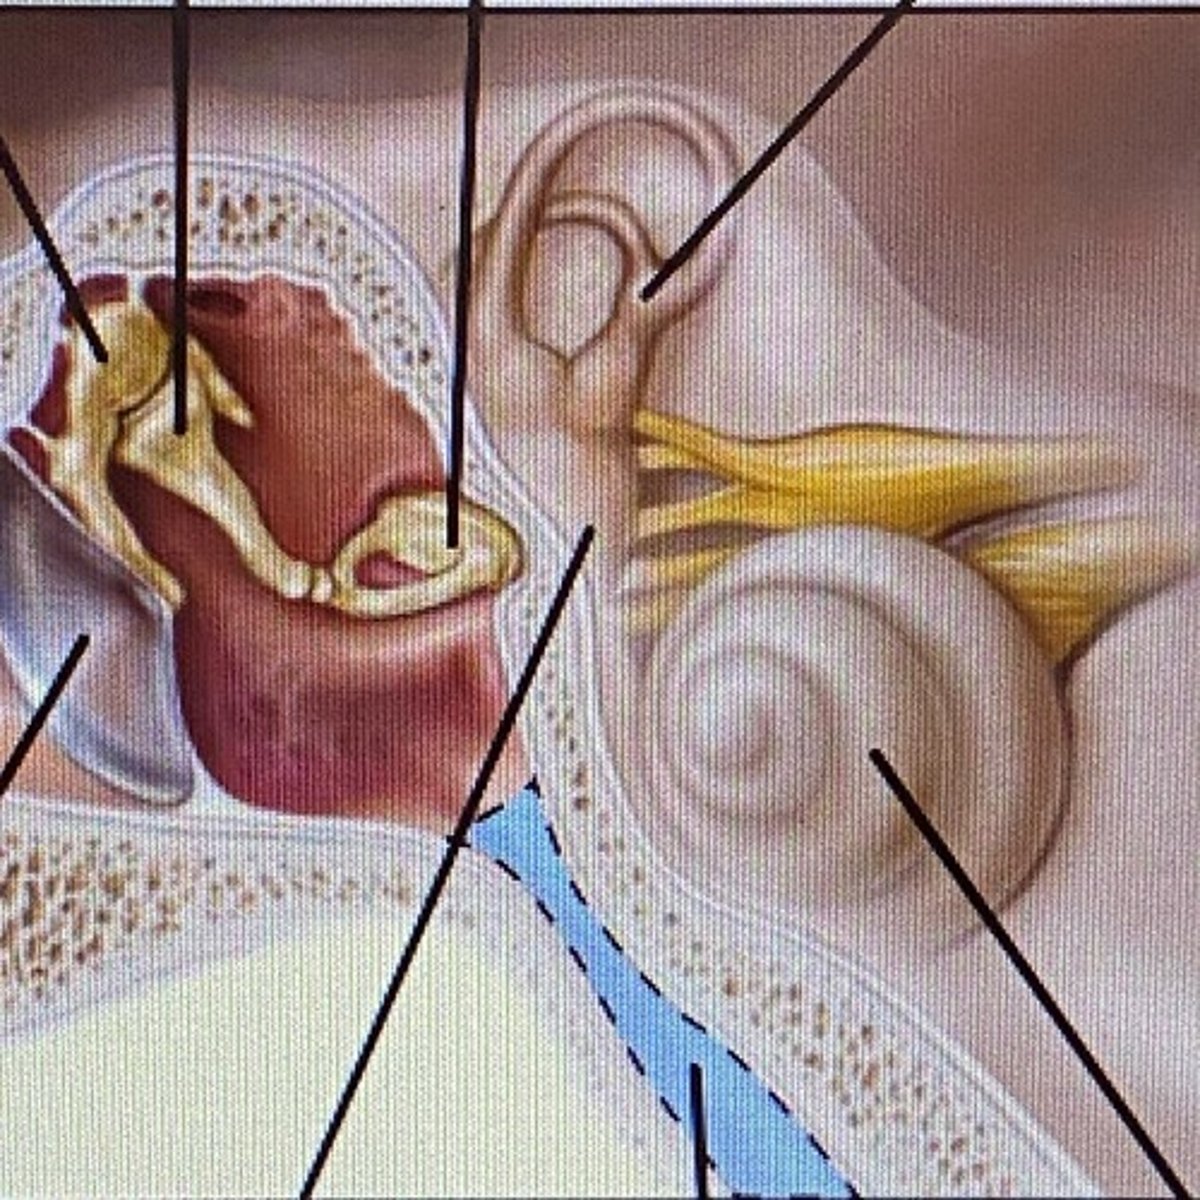

auricle

External Acoustic Meatus

vestibule

-functions in balance and equilibrium

Vestibulocochlear Nerve

- cranial nerve 8

Stapes

Incus

Malleus

Tympanic Membrane

pharyngotympanic tube

external ear

middle ear